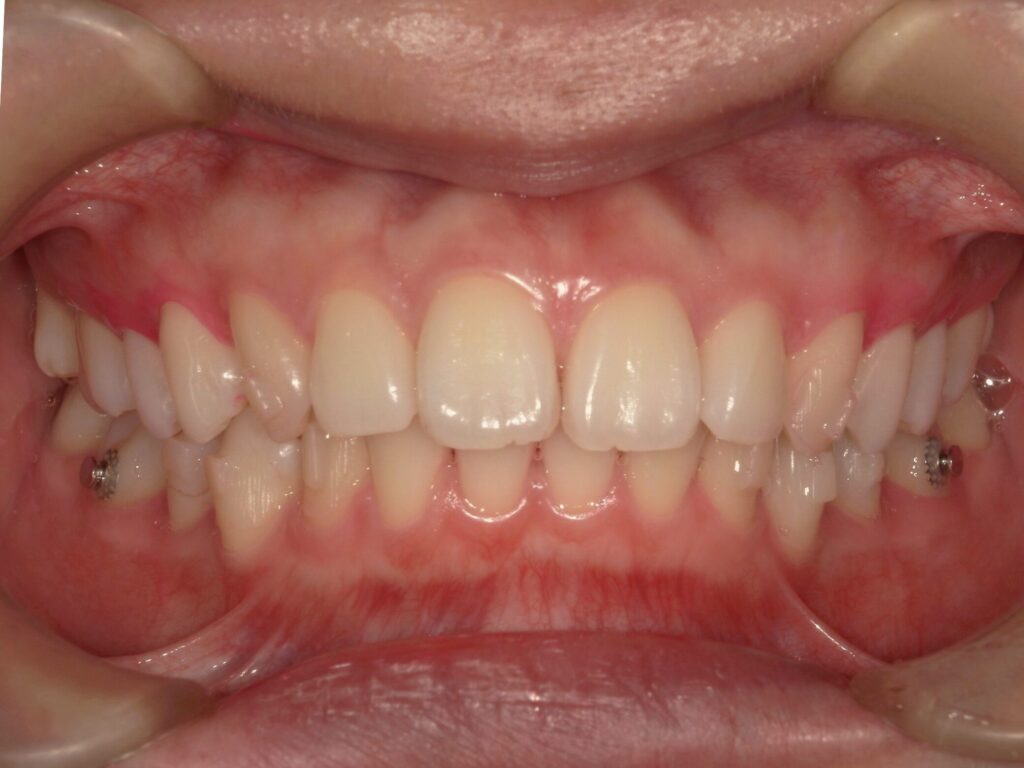

【A様】

Before

After

年齢 | 20代前半 |

性別 | 女性 |

主訴 | 上下の前歯が前に出ている。かみ合わせが悪く、食いしばりをしていて、頬の粘膜に傷ができやすい。 |

施術内容 | アライナー(マウスピース)矯正 |

治療期間 | 10ヶ月 |